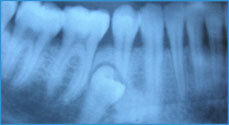

Как поступать с молочным зубом у взрослых, в любом случае нужно решать посте проведения рентгенологического исследования, которое поможет выяснить наличие или отсутствие зачатков непрорезавшегося постоянного зуба, а также то, идет ли процесс рассасывания корня молочного зуба. Если не обнаружены зачатки и не произошло рассасывание корней молочного зуба, при этом он выглядит эстетично и неподвижен, то такой молочный зуб удалять не стоит. То же касается случаев, когда рентгенологически доказано, что положение постоянного зуба такое, что, даже удалив молочный зуб, он не сможет прорезаться. Однако в этом случае лучше проконсультироваться с врачем-ортодонтом.

В том случае, если Вас не устраивает эстетичность молочного зуба или он подвижен, все равно нужно начинать с проведения рентгенологического обследования. Обнаружив на рентгеновском снимке, что нет зачатков постоянного зуба, и произошло рассасывание корней молочного зуба, к тому же наблюдается подвижность 3 – 4 степени (зуб сильно подвижен), то его нужно удалить и дальше принимать решение о том, какой вид протезирования использовать в данном случае.